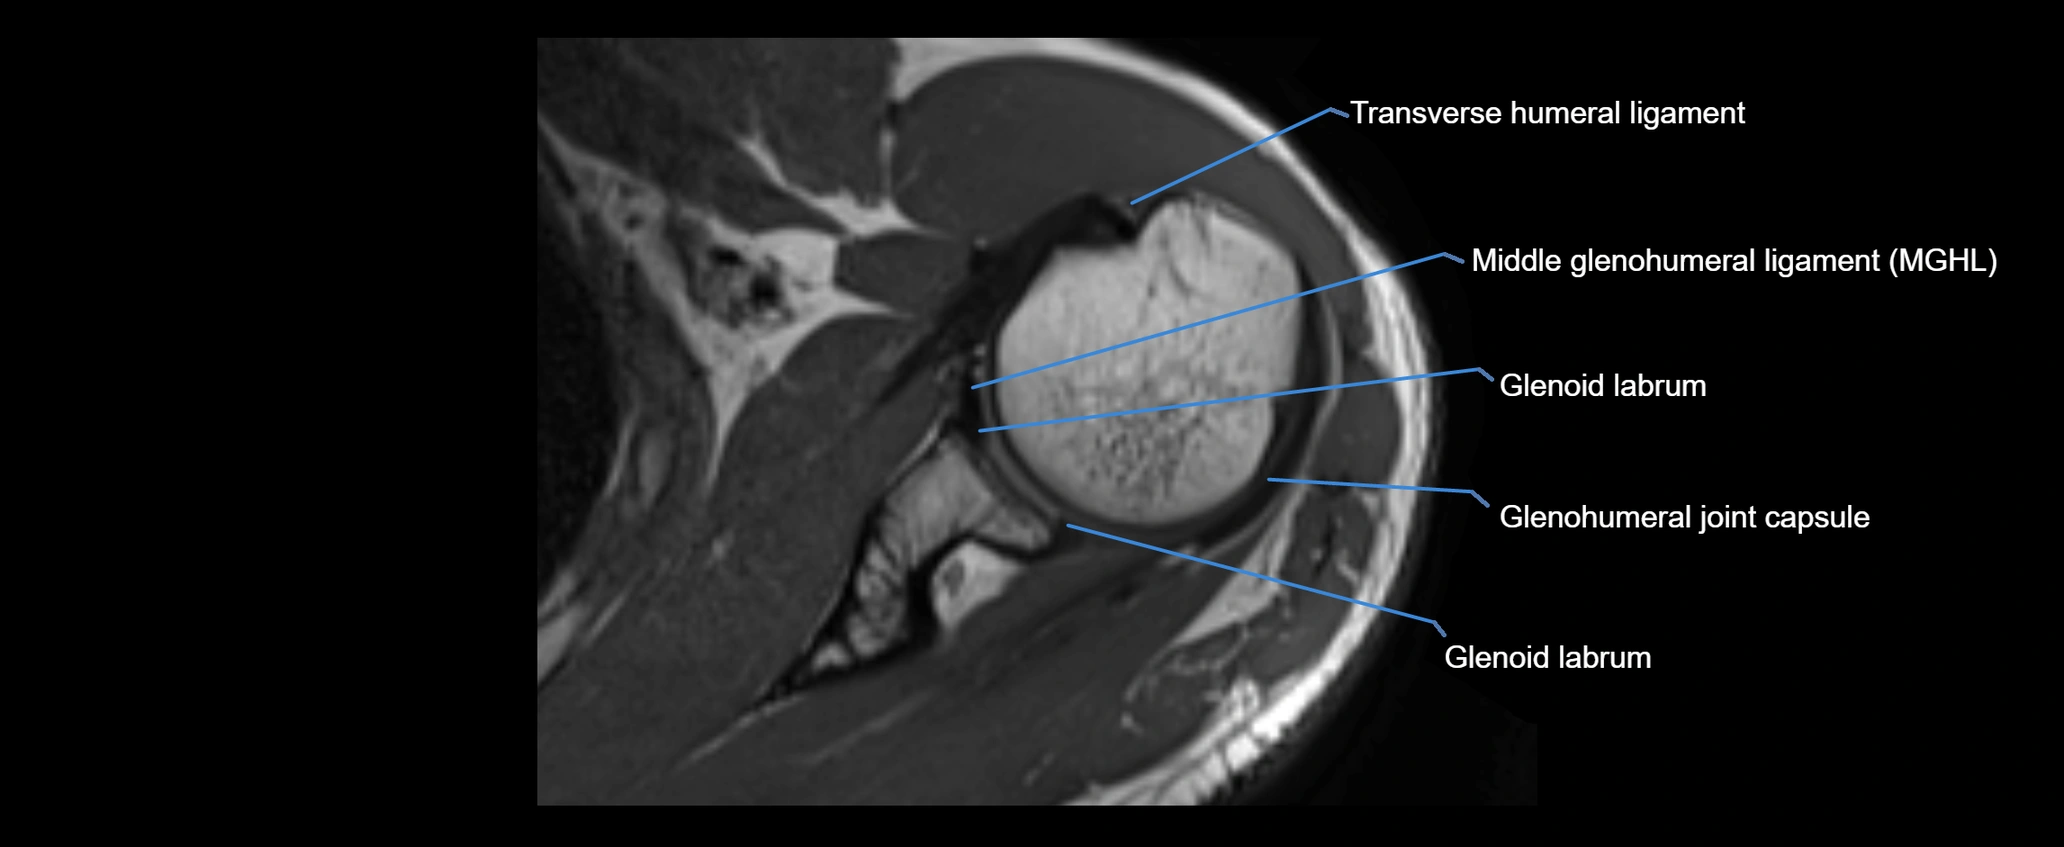

MRI Appearance

• T1-weighted images:

• Normal ligament: Low signal (dark linear band) spanning acromion to clavicle.

• Surrounding fat planes: Bright, delineating the ligament clearly.

• Marrow of clavicle and acromion: Bright due to fatty content.

• Tears: Discontinuity or irregular thickening with intermediate-to-bright signal.

• Chronic injury: Thinning, fraying, or irregular low-signal fibers with adjacent scarring.

• T2-weighted images:

• Normal ligament: Low signal, homogeneous.

• Partial tear or sprain: Focal hyperintensity or thickening.

• Complete tear: Discontinuity with fluid-bright gap between clavicle and acromion.

• Associated edema: Bright signal in distal clavicle or acromion marrow.

• STIR:

• Normal ligament: Dark linear band.

• Injury or inflammation: Bright hyperintense signal in and around ligament fibers.

• Highlights periligamentous soft-tissue edema, especially in acute trauma.

• Proton Density Fat-Saturated (PD FS):

• Normal ligament: Low signal, uniform thickness.

• Partial tear or sprain: Bright signal or contour irregularity.

• Complete tear: Clear discontinuity with bright signal gap and joint effusion.

• Excellent for assessing joint capsule, coracoclavicular ligaments, and periarticular edema.